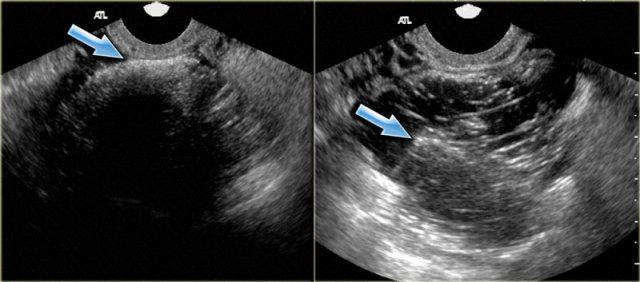

Nang xuất huyết với cục máu đông bắt chước hình ảnh u tân sinh. Lưu ý không có dòng chảy và tăng âm phía sau tốt (mũi tên)

Cục máu đông trong nang xuất huyết đôi khi có thể bắt chước nốt đặc trong u tân sinh. Tuy nhiên, cục máu đông thường có bờ lõm do co rút, trong khi nốt thành thực sự có bờ lồi ra ngoài.

Trong cả hai trường hợp, sẽ không có dòng chảy nội tại trên siêu âm Doppler và có tăng âm phía sau tốt.

Hình ảnh siêu âm cho thấy nhiều nang đơn giản và một nang phức tạp ở buồng trứng phải, với hồi âm mức độ thấp lan tỏa và không có dòng chảy trên siêu âm Doppler.

Lưu ý có tăng âm phía sau tốt, kể cả qua nang phức tạp (mũi tên xanh).